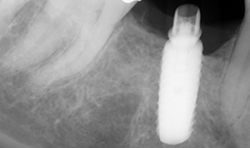

A digital periapical X-ray (PA) (Fig. 12) was taken using Air Techniques ScanX phosphor plates. The PA revealed caries into the pulp. The tooth would require endodontic therapy, a post core and a crown.

Fig. 12 Fig. 13

Root canal therapy was completed (Fig. 13).